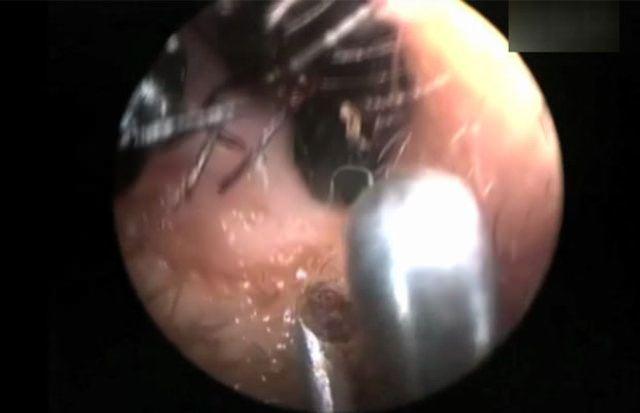

Kulağından binlercesi çıktı!

Dr. Jawahar, "Shreya'nın ailesi normal bir hayat sürüyor ve sağlıklı bir çevrede yaşıyor. Bu sebeple yaşam şartlarının da bu duruma sebep olduğunu iddia edemeyiz.